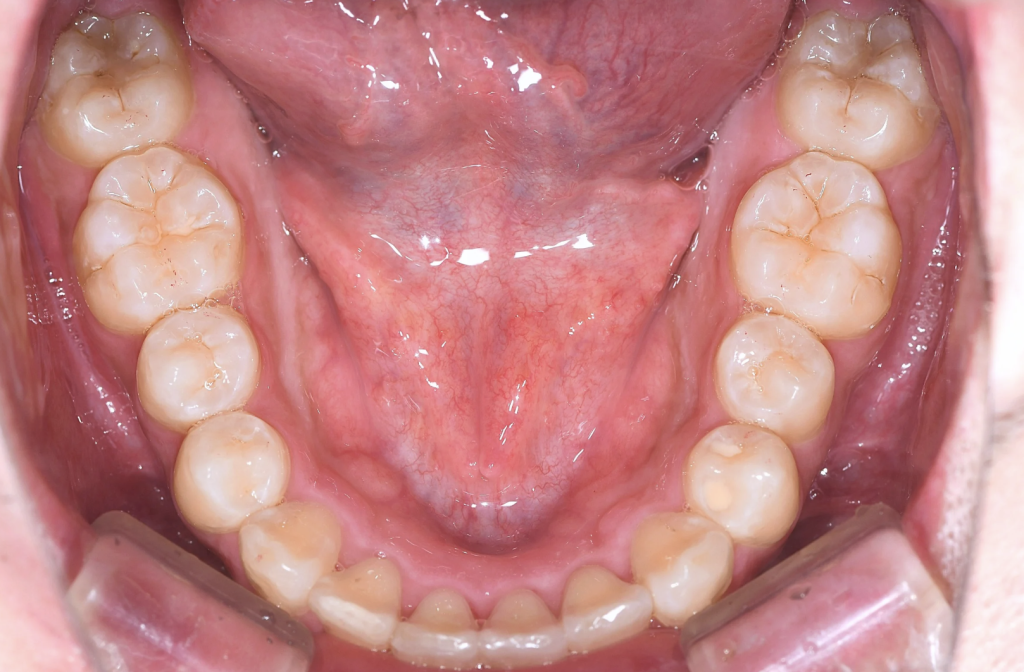

永久歯に大きさに対し、歯を並べるスペース(顎)が小さく、

上下ともに狭窄歯列、下顎前歯には叢生(歯のガタつき)、上顎前歯の突出感が認められました。